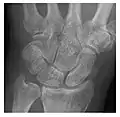

Occult osseous injuries may result from a direct blow to the bone by compressive forces of adjacent bones against one another or by traction forces during an avulsion injury. Lesions in the tibial plateau, hip, ankle, and wrist are often missed. In a tibial plateau fracture, any disruption of the posterior and anterior cortical rims of the plateau should be sought. Impaction of subchondral bone will appear as an increased sclerosis of the subchondral bone (Figure 1). In the hip, posterior acetabular fractures also present subtle radiographic findings. The acetabular lines should then be carefully examined keeping in mind that the posterior rim, which is harder to see on X-rays, is more frequently fractured than the anterior rim (Figure 2). In the wrist, detection of carpal bone fractures is often challenging, with up to 18% of scaphoid fractures radiographically occult. Carpal fractures, especially the scaphoid, are associated with the risk of avascular necrosis. In apparently normal wrist radiographs from symptomatic patients, if there is history of a fall on an outstretched hand with pain in the anatomic snuffbox, suggesting scaphoid injury, the initial examination with posteroanterior, lateral, and pronation oblique views must be complemented by other specific views such as supination oblique and the "scaphoid" view A careful examination of cortices for evidence of discontinuity or offset and cancellous bone for lucency is necessary (Figure 3).[1]

Figure 3: A 26-year-old man presenting with wrist pain after being assaulted. (a) Initial anteroposterior radiograph shows a subtle linear lucency within the scaphoid extending to the scaphocapitate articular surface that was overlooked (arrow). (b) Initial "scaphoid" view was negative. (c) Followup anteroposterior radiographs, 12 days later, shows obvious scaphoid fracture (arrows).[1]

Triquetral fracture usually occurs on the dorsal aspect by impingement from the ulnar styloid or avulsion of strong ligamentous attachment. The dorsal avulsion fracture or "chip fracture" appears as a small bony fragment on the dorsal aspect of the triquetrum and is best detected on the lateral view(Figure 4). When radiography is negative in patients with high suspicion of a fracture, both MRI and MDCT will be of value. However, it has been shown that MRI is superior for detecting trabecular fractures in carpal bones.